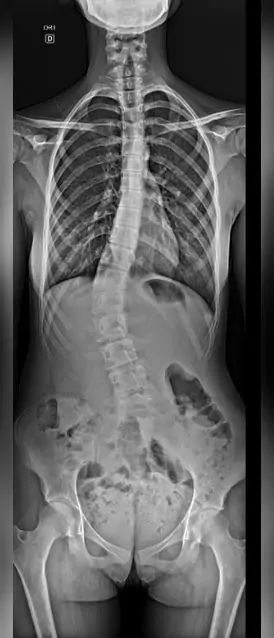

Olha o raio x ☢️ Incidência panorâmica total de coluna para escoliose.